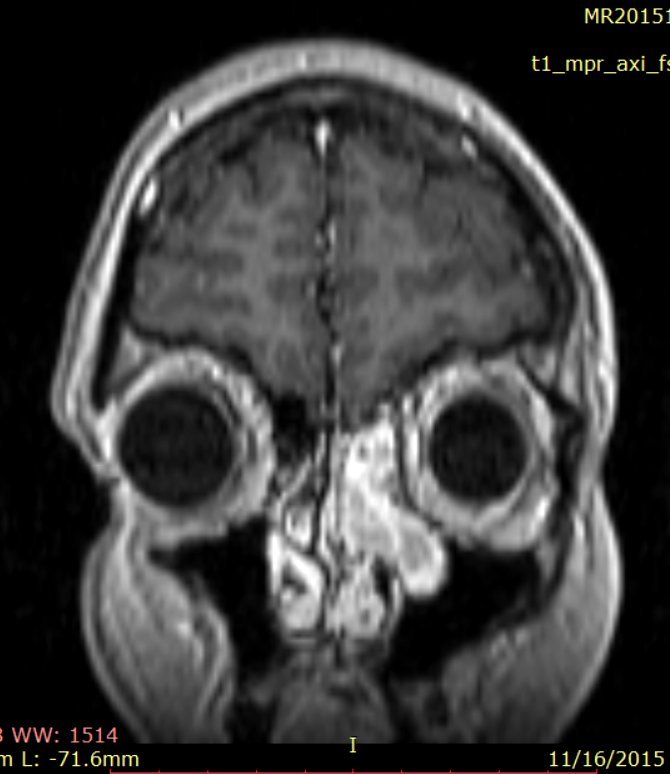

RMN cu substanţă de contrast efectuat postoperator confirmă existenţa unei restanțe tumorale cu un volum de aprox. 10% din volumul tumoral iniţial, situată în canalul nazofrontal stâng şi în sinusul frontal stâng (fig. 3).

Fig.3: RMN postoperator: restanta tumorala localizata in canalul nazofrontal stg